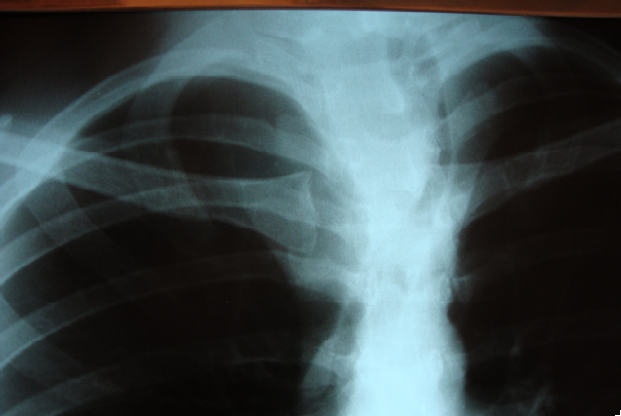

Devido ao crescimento rápido de lesão cervical que, atualmente, apresenta o tamanho de 10 cm x 6 cm, associada à perda ponderal de seis kg, nos últimos quatro meses, um homem de 30 anos de idade procurou o ambulatório de cirurgia geral. Relata nódulo tireoidiano, descoberto há quatro anos, em lobo direito, que era assintomático. Realizou punção biópsia com agulha fina guiada por US que revelou tumor folicular. No momento, a dosagem hormonal é normal e nega sintomas compressivos. O paciente realizou radiografia de tórax que pode ser visualizada abaixo.